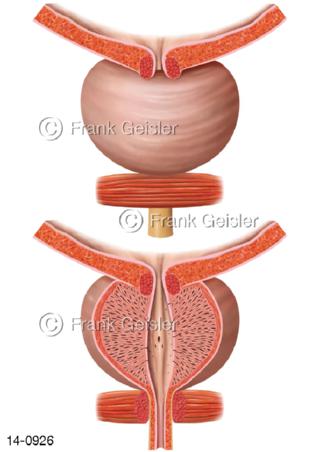

Bildergalerie Urogenitalsystem

Bilder zum Urogenitalsystem mit Urogenitalorgane, Urogenitaltrakt, zum Harn- und Geschlechtsapparat, Harnorgane und Geschlechtsorgane, Organe der Harnwege und der Fortpflanzung, Harnorgane und Geschlechtsorgane im männlichen und weiblichen Urogenitalsystem